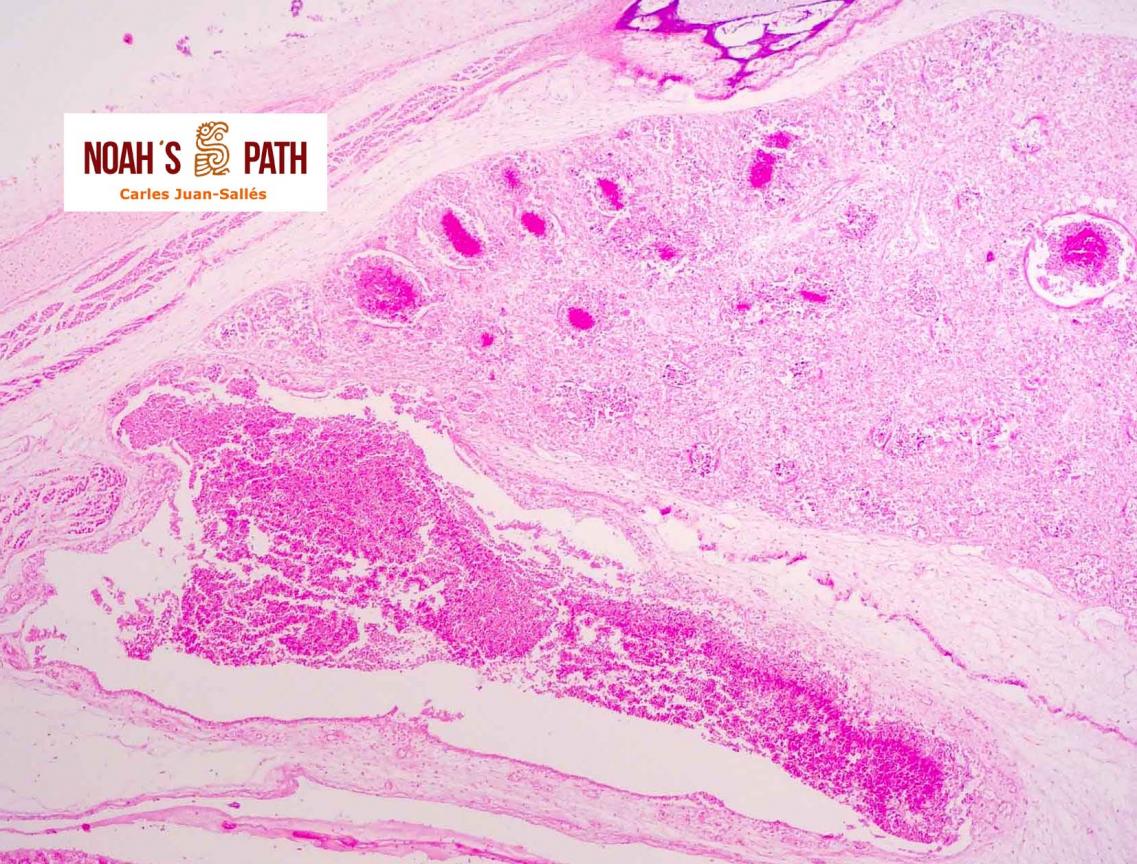

Tauraco fischeri

Hemorragias subcutáneas

Cacatúa